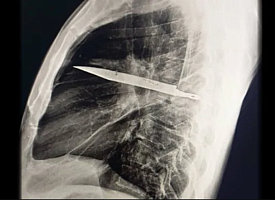

Мужчина 8 лет ходил с лезвием ножа в груди и не замечал этого